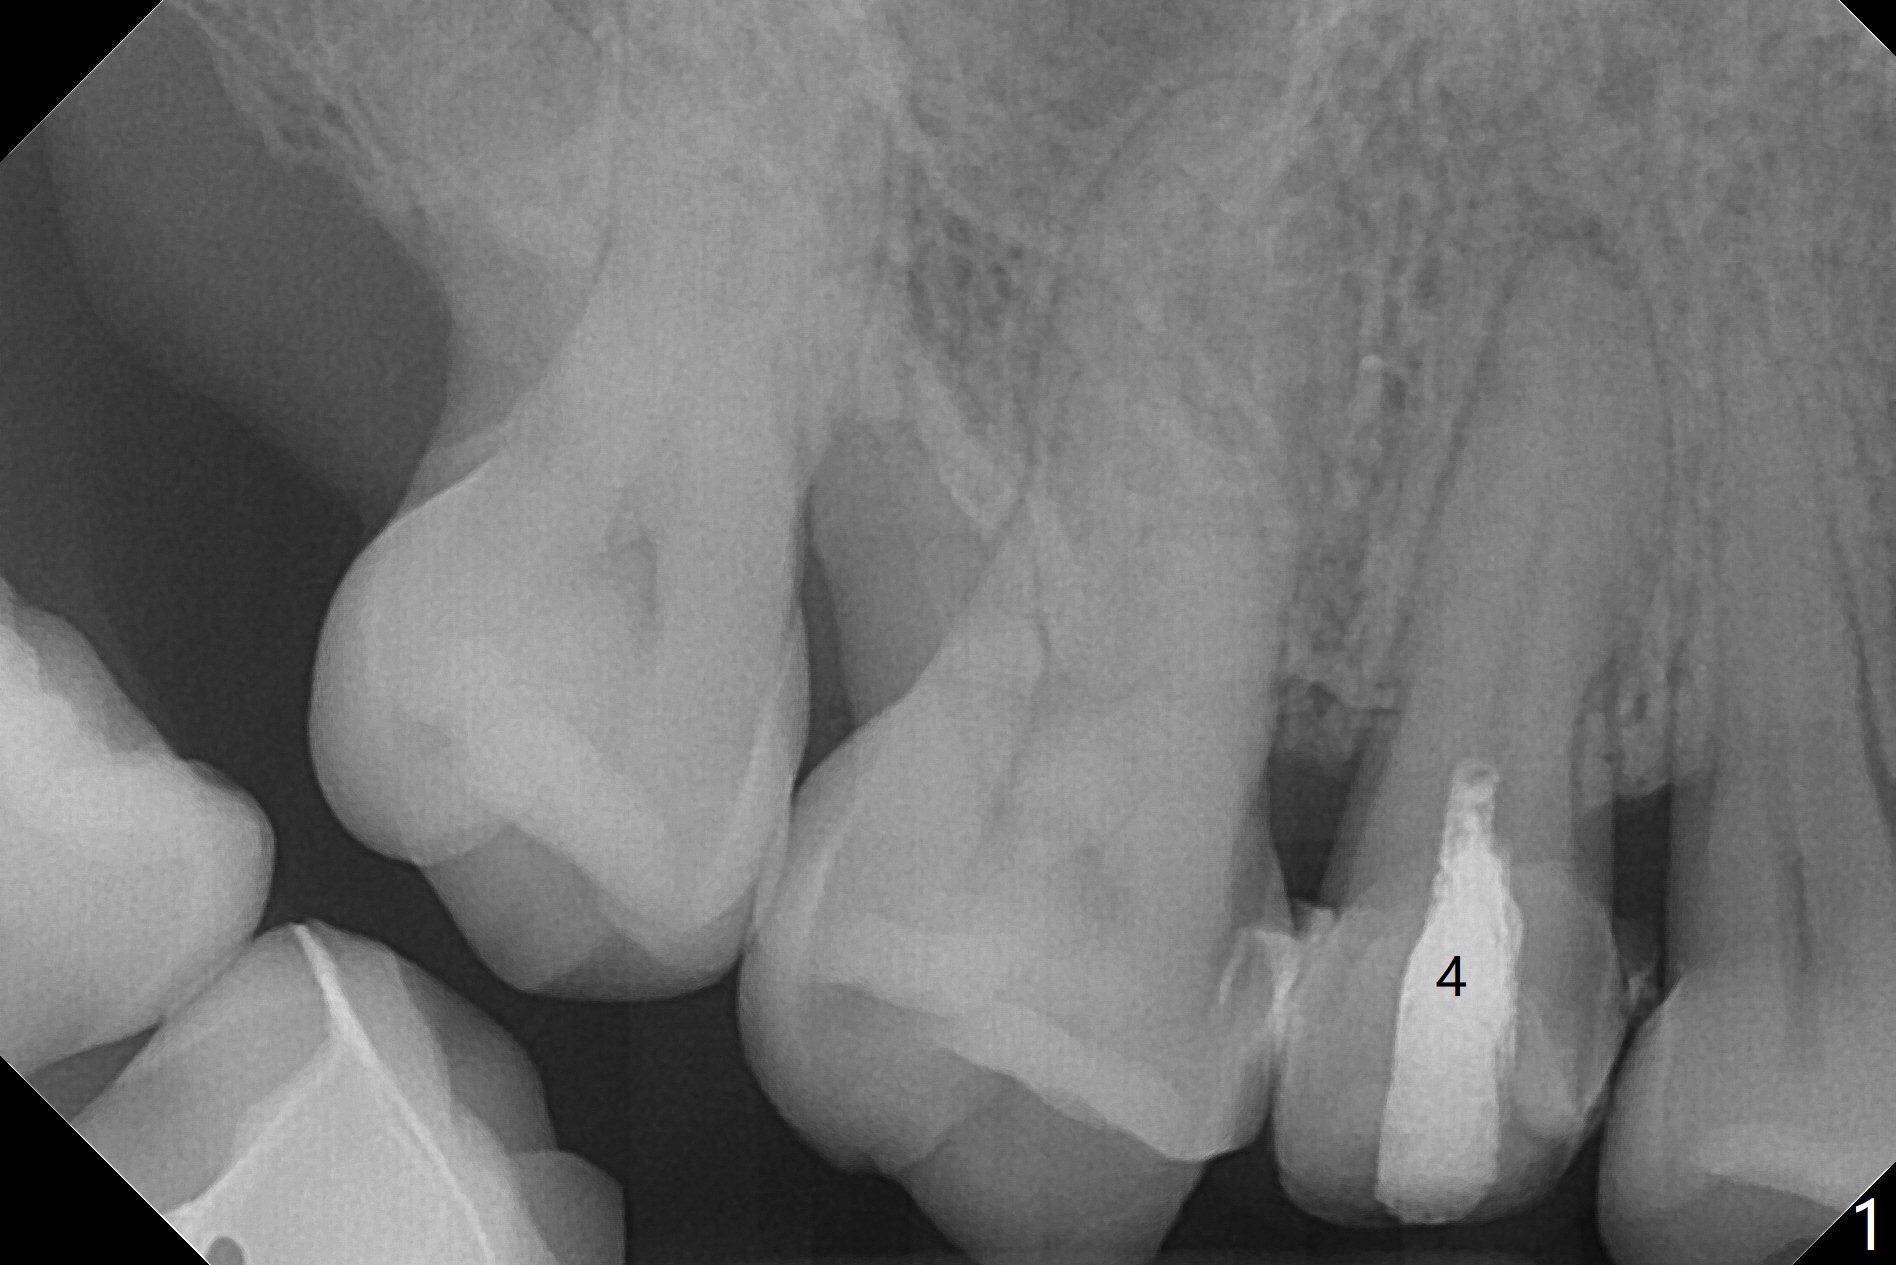

52岁女去年在外州开始4号牙根管治疗(图一),